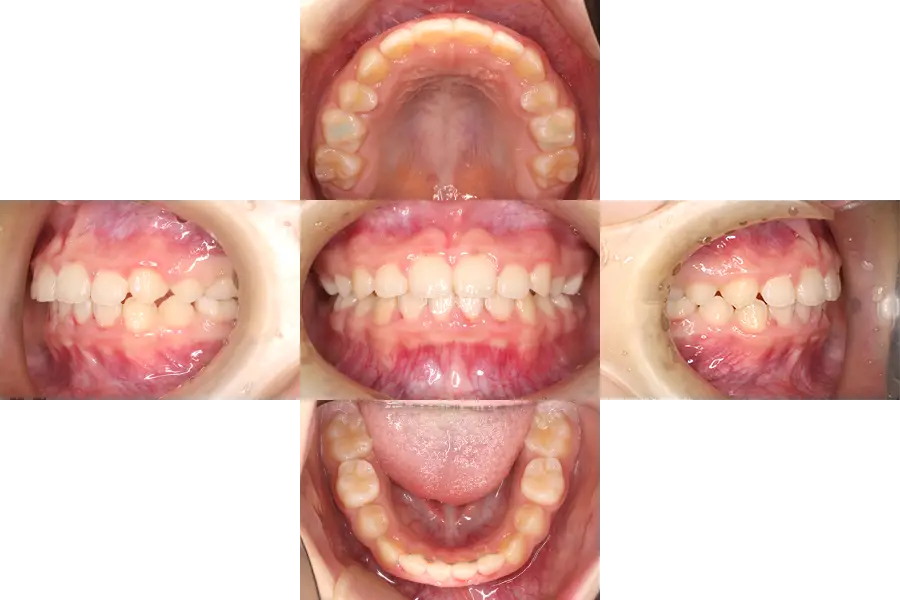

非対称の小児矯正治療例

- 主訴

- 前歯の凸凹、永久歯が生える隙間がないと指摘された

- 治療開始年齢

- 10歳

- 診断

- 凸凹、歯の大きさに対して顎が小さい、過蓋咬合

- 難易度

- 軽度

- 使用した装置

- 歯列側方拡大装置、唇側ブラケット装置

- 治療期間

- 約1.0〜1.5年

- 費用(税込)

-

基本料金 399,300円 調整料(約12〜18回) 来院ごと6,600円 総額 478,500円~

- 治療について

初診時には、前歯部の凸凹と過蓋咬合、レントゲン写真より上顎両側犬歯のスペース不足と萌出方向異常などが認められました。

まず初めに、上下歯列に歯列側方拡大装置を入れ、犬歯の萌出スペースを確保および前歯部凸凹改善のためのスペースを確保しました。

十分にスペースを確保できたのち、前歯部にブラケット装置を付け、前歯部の歯並びと咬合を改善しました。

1期治療終了後、永久歯の生え変わりと顎の成長による変化を観察しておりましたが、それらの成長変化が終了した段階(1期治療後5年経過時)でも、良好な歯並び・咬合が得られています。

- 治療のリスク

違和感、痛み、しゃべりにくさ、歯磨きの難しさ、虫歯のリスク増大、矯正装置の脱落、顎の成長や歯・顎の大きさによっては2期治療で小臼歯等の抜歯が必要になる可能性、自費診療。